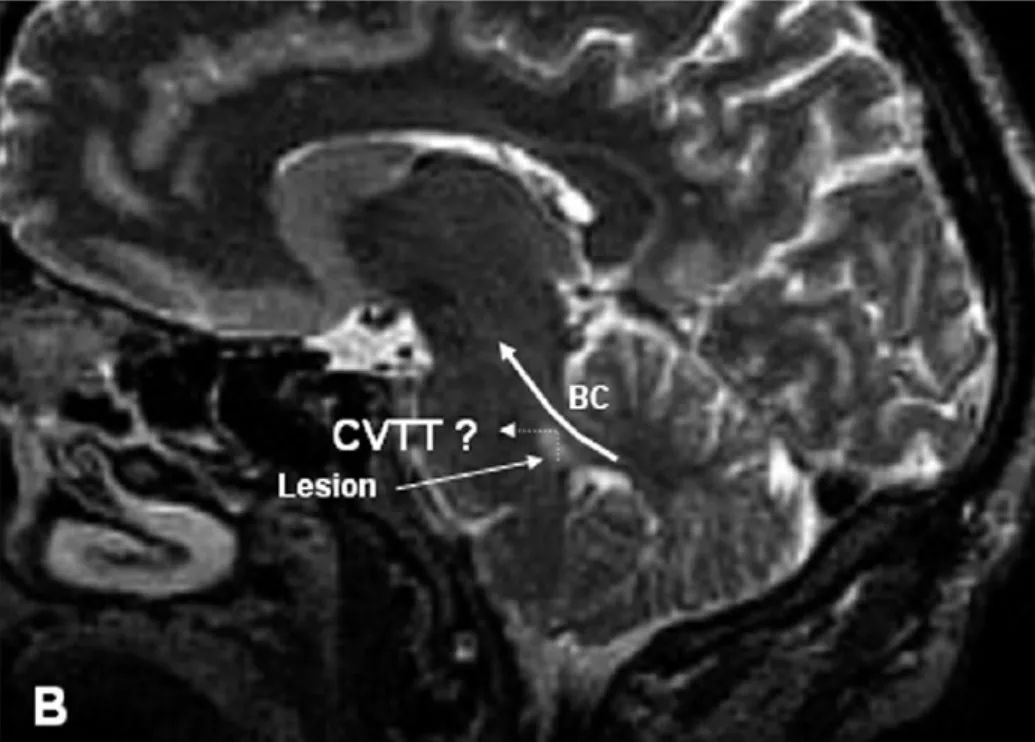

在最近的PPUN病历报道中,损伤都非常小(图2A),可能恰好位于CVTT交叉部(图1)。恰好位于脑桥中段水平,考虑人类的CVTT交叉位于脑桥基底部的后界处,而不是位于脑桥被盖前部。该患者中,上向VEM的增益降低,大约是下向VEM的一半。因此认为CVTT不仅参与上向EP信号的传递,还参与上向VEM信号的传导。在PPUN的另外一个病例中,损伤可能累及了SVN的上极和CVTT的初始段(位于脑桥被盖下段的后-外侧部)(图1和2B)最后,另外一个PPUN的病历的损伤部位位于中脑被盖的前部,考虑可能是类似于猫的CVTT终段处的损伤(图1)。这些证据集合起来可以作为证据证明在人类,CVTT在传导上向兴奋性EP和VEM信号中起重要作用。

图2 导致PPUN的小的脑桥损伤。 A、水平位显示(MRI,T2)单侧损伤,恰好位于脑桥中段水平,在左侧脑桥基底的后-旁中央部。B、矢状位(MRI,T2)显示单侧损伤,累及右侧脑桥被盖下段的后-外侧部,BC未累及。